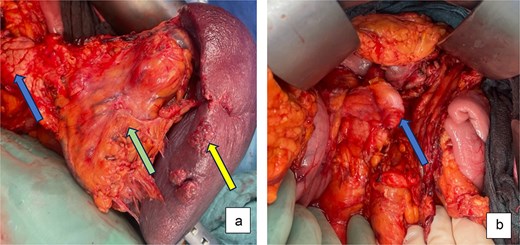

Because of the high rupture risk and potential exsanguination, an urgent open distal pancreatosplenectomy was performed after informed consent. A midline laparotomy provided rapid exposure and vascular control. Intraoperatively, a pulsatile giant SAA occupied the hilum and displaced the pancreatic tail. After entering the lesser sac, the proximal splenic artery was isolated along the pancreatic superior border and centrally ligated. The gastrocolic ligament and short gastric vessels were divided, the stomach retracted cranially, and the spleen mobilized en bloc with the involved pancreatic tail (Fig. 2a). The splenic artery was transected distally, and the splenic vein was ligated. The pancreas was transected after gradual compression over 3 min at the level of the mesenteric-portal axis using an Endo-GIA 60 mm stapler. No bleeding was seen from the pancreatic capsule. A ligamentum teres patch was sutured to the pancreatic stump to reduce the risk of postoperative pancreatic fistula (Fig. 2b). Two passive silicone drains were placed—one at the pancreatic transection site and one in the left lower abdomen.

Intraoperative pictures: (a) After dissection and exposure of the giant SSA (green arrow) attached to spleen (yellow arrow) and distal pancreas (blue arrow) and (b) after distal pancreatosplenectomy with ligamentum teres patch on pancreatic stump (blue arrow).